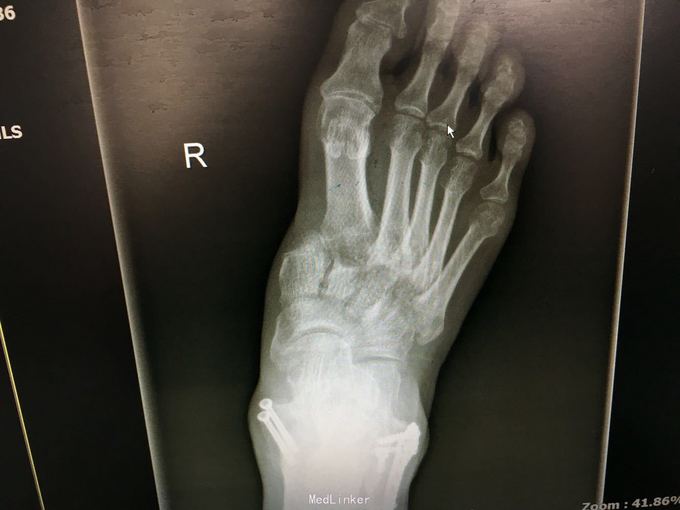

查体:左肾区叩痛,无皮肤隆起,未扪及肿块;腰椎压痛,活动受限,双下肢感觉存在,右小腿石膏托外固定,有踝关节明显肿胀,局部压痛活动受限,指端感觉血运可。 CT及X片:L2、L4椎体爆裂性骨折,L1-L4左侧横突骨折,右坐骨支骨折,右侧胫骨内、后及右侧腓骨外踝骨折,右足第1-4跖骨向外侧脱位及半脱位,伴近端斯脱性骨折。左肾挫裂伤,左肾重度积水,左肾周血肿。

诊断:右足lisfrance损伤,左肾挫裂伤;左肾周血肿,左侧输尿管结石伴左肾重度积水,L2、L4椎体骨折,L1-L4左侧横突骨折,右侧坐骨支骨折,右三踝骨折,全身多处皮肤软组织挫伤 处理:急诊行左肾探查,左肾切除术,择期行经后路腰2、4椎体骨折切开复位、椎公根螺钉内固定术+右内、外踝骨折切开复位内固定术,择期行右足lisfrance关节复位克氏针内固定术。